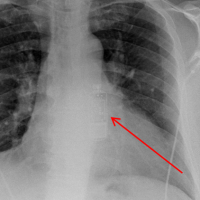

Auch diese Operation kann im Herzkatheterlabor vorgenommen werden. Zusätzlich zu den Sonden eines Herzschrittmachers bzw. Defibrillators wird eine weitere Sonde (Elektrode) über Venen des Herzens, die in den rechten Herzvorhof münden, auf die linke Seite des Herzens vorgeschoben. Dazu stellt sich ihr Arzt die Venen mit Kontrastmittel unter Röntgenkontrolle dar. Die Dauer eines derartigen Eingriffes ist mit 1,5-3 Stunden länger als die einer klassischen Herzschrittmacher- oder Defibrillatoroperation. In der Regel schläft der Patient daher bei diesem Eingriff.